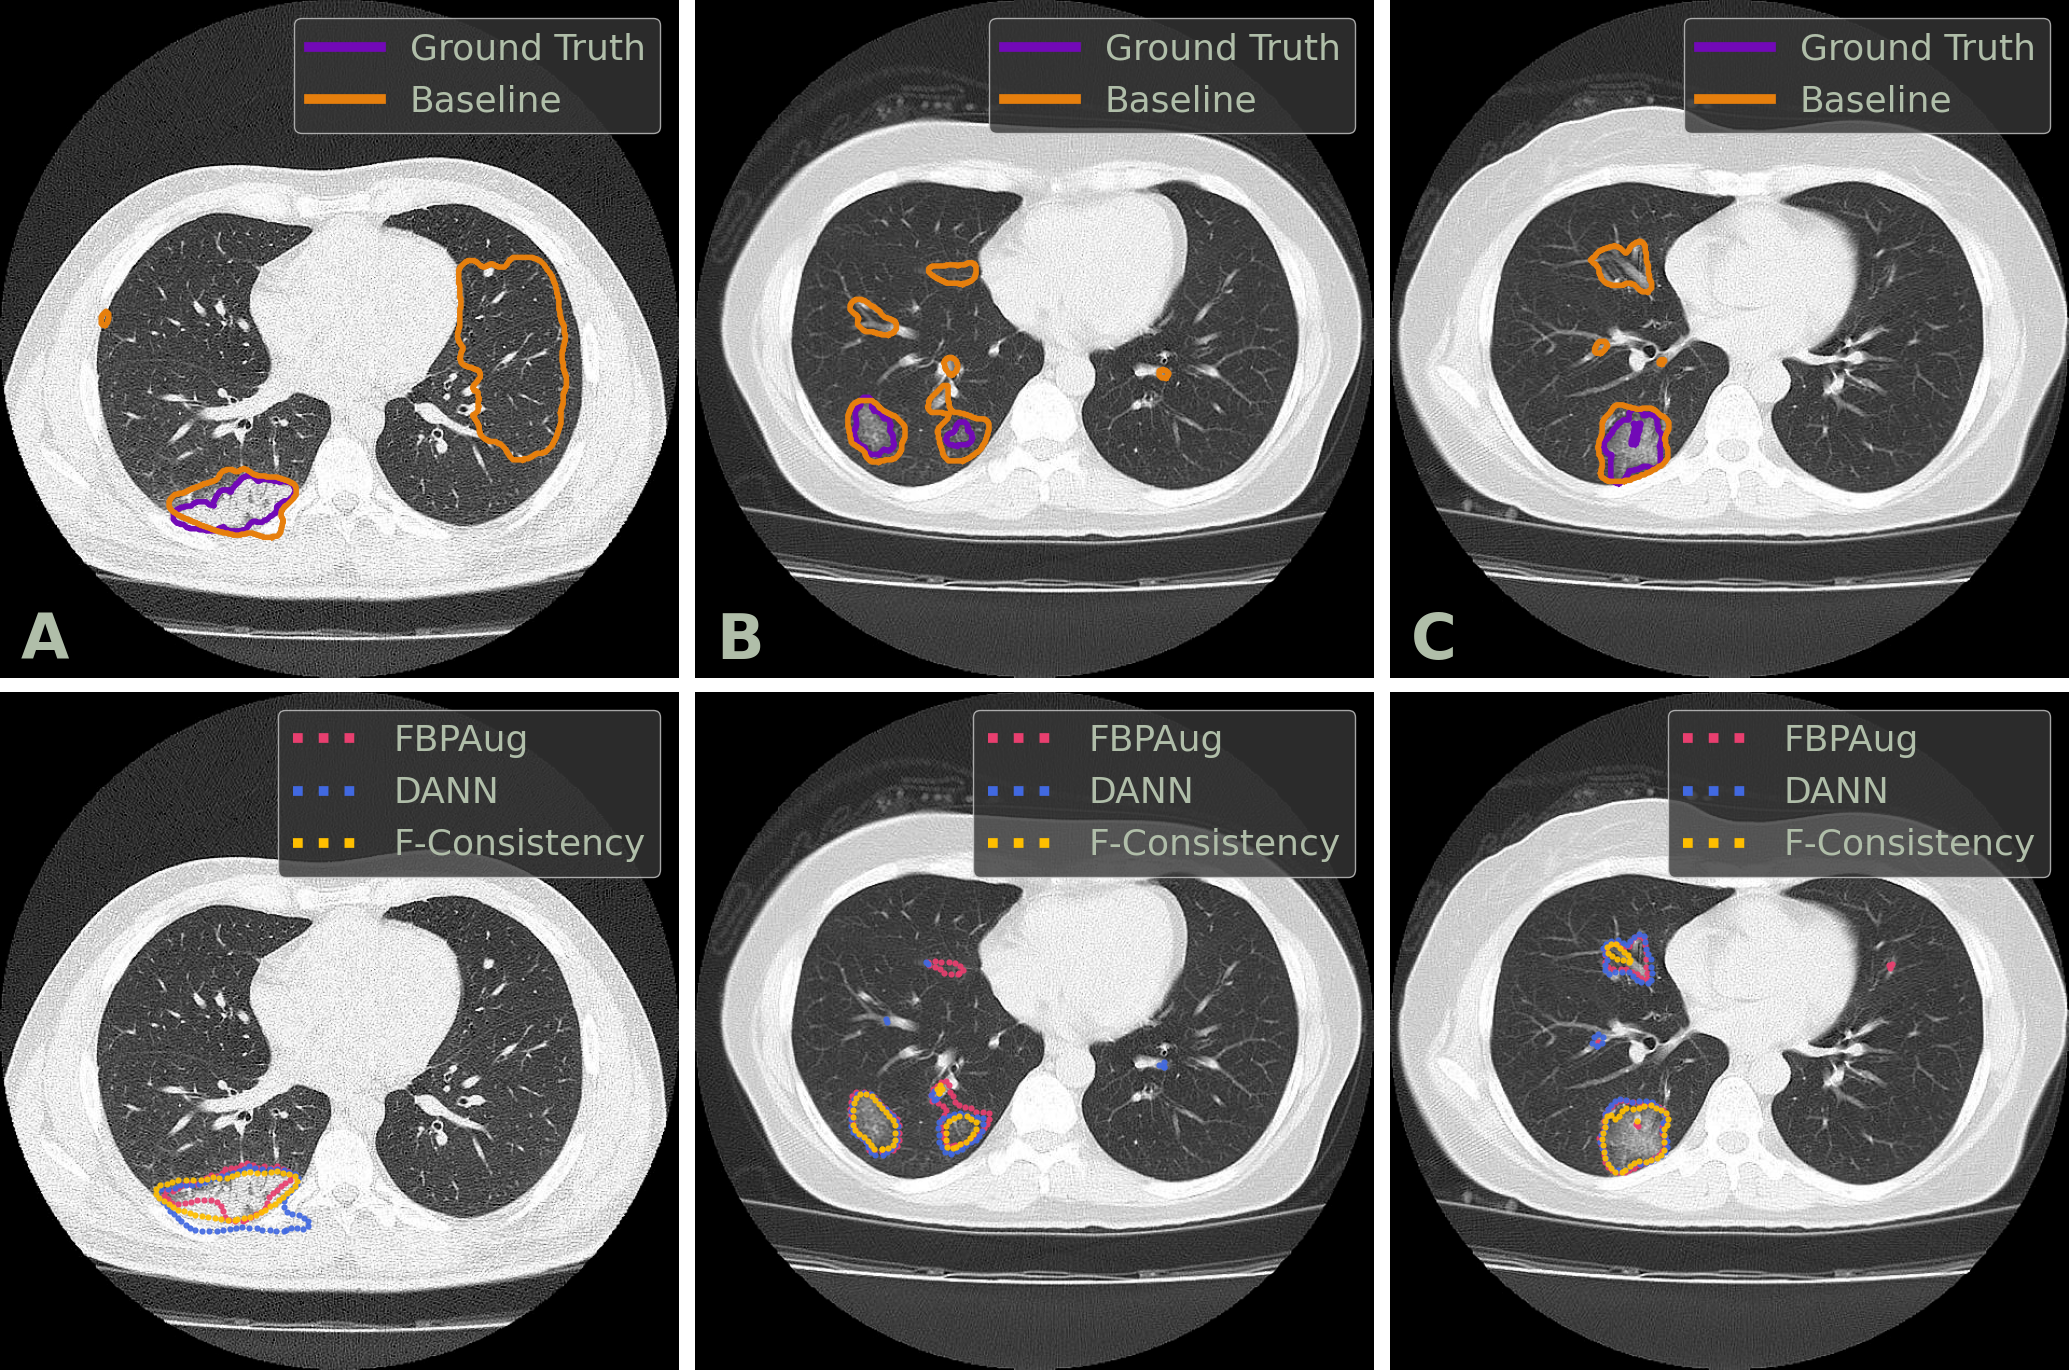

We conclude the comparison of the methods comparison with the qualitative analysis. In Fig. 2, one could find examples of the Baseline, FBPAug, DANN (Enc), and F-Cons (Enc) predictions on the COVID-test dataset and compare them with the ground truth. Although all adaptation methods perform similar to the ground truth with minor inaccuracies, Baseline outputs the massive false positive predictions on the unseen domain. Additionally to the quantitative analysis above, the latter observation highlights the relevance of the domain adaptation problem in the COVID-19 segmentation task.

In Fig. 3, we visualize predictions of the same four methods on the paired images from the Paired-private dataset. For the Baseline, we observe an extreme inconsistency (Fig. 3, A) and massive false positive predictions in healthy lung tissues (Fig. 3, D) and even outside lungs (Fig. 3, B). For the adaptation methods, their predictions are visually more consistent inside every pair, which aligns with the consistency scores in Tab. 3. Despite the high consistency scores, FBPAug and DANN output perceptually more aggressive predictions. FBPAug predicts motion artifacts near the body regions (Fig. 3, A) and triggers similarly as the baseline on, most likely, healthy lung tissues (Fig. 3, B). DANN is more conservative but triggers on the consolidation-like tissues (Fig. 3, C and D). However, without the ground truth annotations on the paired data, we refer to this analysis as a discussion.